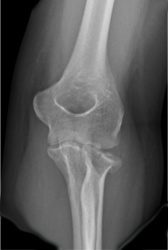

1a. Displaced, multifragmentary fracture of the radial head

A rotation of the displaced, multifragmentary fracture